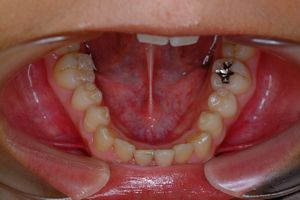

治療前 の 下アゴ です 動く矢印治療後 の 下アゴ です